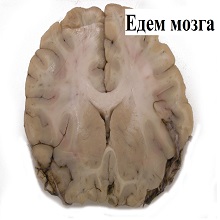

Едем мозга представља повећање укупне запремине мозга услед накупљања воде у интра- или екстрацелуларном простору можданог ткива. Идентификоване су три врсте можданог едема – цитотоксични, вазогени и интерстицијални, мада је у клиничким условима њихово разликовање ретко могуће због њиховог преклапања у истој патолошкој ситуацији. |